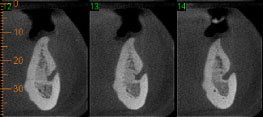

Caso2: Localização de dente retido

História clínica de exodontia do dente 38 há um ano, sem no entanto localizar o elemento dentário acreditando que o paciente havia engolido o dente. Na radiografia panorâmica observa-se a presença do dente 38 superposto ao ramo. Na tomografia localiza-se o dente no assoalho bucal.